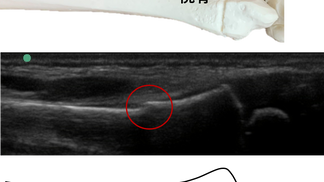

症例〈橈骨遠位端部若木骨折〉

2020年4月9日